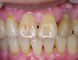

Treatment of gum disease : Teeth with periodontitis are maintained for long time by a periodically scaling and root plaining (pocket maintenance) . Periodical cleaning of the periodontal sulcus would remove bacterias , and stimulate tissue regeneration .

Teeth whitening and Gum bleech: Whitening of teeth are practiced at our clinic , or home . Melanaization parts of gum can be removed by medicine , that would lead to regeneration of healthy colored gum .

Passing 40 years old , probability of missing tooth caused by periodontitis is statistically rising . Periodontitis is chronic disease , and once having this , complete cure could be difficult . Therefore , cleaning of periodontal sulcus where is difficult to be cleaned with toothbrushes should be done periodically in dental clinic .

As a consequence of this process , the periodontal disease could be cured , but in case of the remaining of periodontal pocket , a periodical maintenance of the periodontal disease in dental clinic would be indispensable. Maintenance schedule will be planned by the extent of periodontal disease , the condition of brushing , and your opinion . We recommend every 3 months visit basically , but maintenance program would vary from every month to half a year , thinking highly of your request .

If you have foul breath , discomfort in mouth , bleeding or swelling of gum , tooth mobility , please don`t hesitate and consult with us .